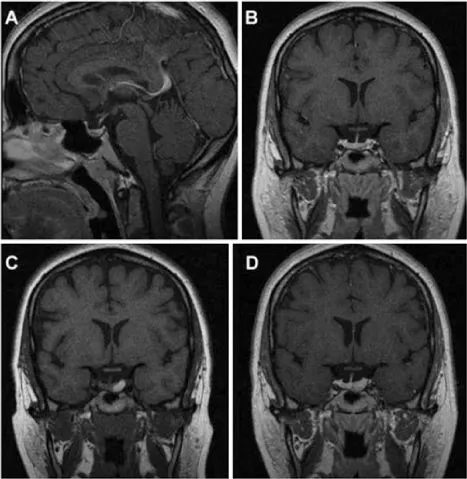

图1展示了一名27岁女性患者的MRI资料,该患者因垂体微腺瘤接受William T. Couldwell教授的随访监测,后续发生垂体卒中。

A、B图为初次就诊时获得的矢状位与冠状位T1加权增强MRI,显示垂体左侧部一小腺瘤。

C、D图为随后复查的冠状位T1加权平扫及增强MRI,可见原肿瘤区域出现出血信号,提示腺瘤内卒中。